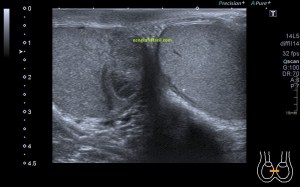

Al llegar al compartimento 6 me encuentro un tendón engrosado de tamaño y aspecto heterogéneo típico de afectación por tendinosis, con líquido en la vaina, te lo señala la imagen con flecha amarilla. Lo recorro y confirmo los hallazgos eje corto y eje largo, hago medidas y compruebo el doppler que marca Neovascularización asociada.

Observa las tres imágenes superiores, son muy ilustrativas, son comparativas de normalidad hallazgos patológicos, el izquierdo claramente patológico y el derecho claramente normal.